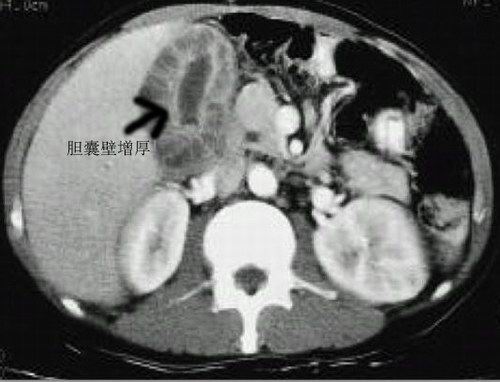

膽囊結(jié)石CT影像表現(xiàn)一般有膽囊增大、膽囊壁增厚、膽囊高密度影等情況。下面我們?cè)敿?xì)介紹一下: 1、膽囊增大:膽囊結(jié)石一般與肥胖、妊娠、高脂肪飲食等因素有關(guān),臨床癥狀多表現(xiàn)為上腹疼痛、惡心、嘔吐等。如果患者長(zhǎng)期高脂肪、高糖飲食,可能會(huì)導(dǎo)致體內(nèi)血糖升高,導(dǎo)致血液黏稠增加,容易使膽固醇與膽汁酸濃度改變,導(dǎo)致膽汁無法排出,淤積在膽囊內(nèi),從而造成膽囊增大。 2、膽囊壁增厚:膽囊結(jié)石如果不及時(shí)消除或取出,可能會(huì)刺激膽囊壁,引起炎癥反應(yīng),導(dǎo)致膽囊壁水腫。通過CT檢查時(shí)可明顯發(fā)現(xiàn)膽囊壁增厚。

3、膽囊高密度影:如果膽囊炎不及時(shí)治療,可能會(huì)加重膽囊結(jié)石,出現(xiàn)實(shí)質(zhì)性占位病變,進(jìn)行CT檢查時(shí),可明顯看出,呈現(xiàn)高密度影。 |